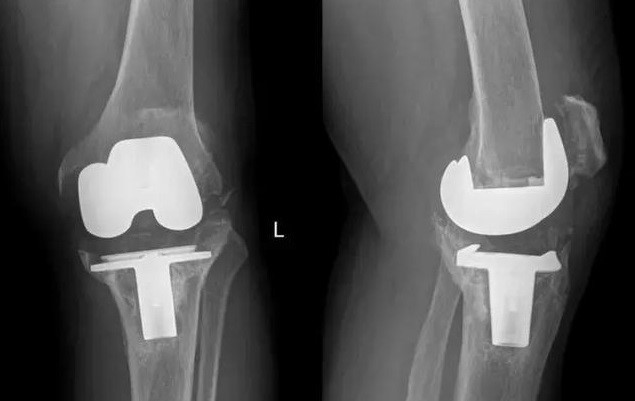

201711月,我國完成了全球首例個性化3D打印鉭金屬墊塊植入的全膝關節(jié)翻修手術;2018年,LPW科技公司與環(huán)球先進金屬集團有限公司(GAM)宣布達成合作協(xié)議,圍繞金屬鉭的增材制造技術可為醫(yī)療外科、牙科、軍事、航空航天以及其他市場領域提供服務。鉭金屬通過3D打印制成的多孔鉭植入體,相較常見的多孔鈦植入物,具有更好的生物力學適配性、并具有接近人骨的彈性模量。在植入穩(wěn)定性上,具有較大優(yōu)勢。